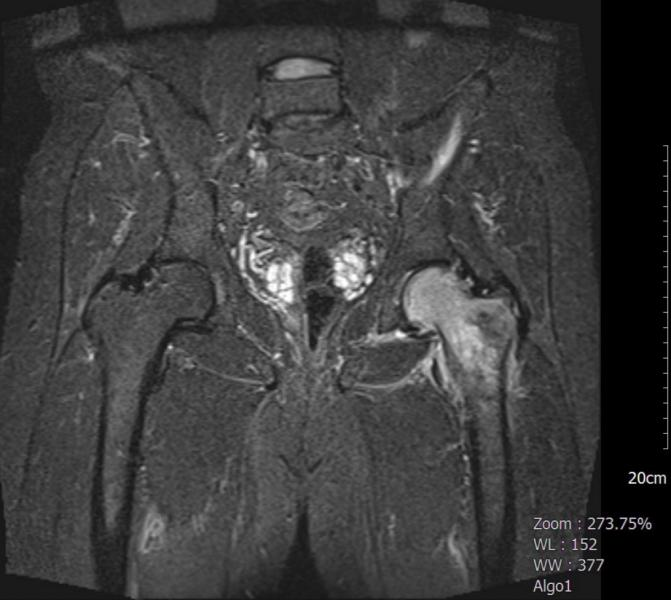

MRI显示股骨头和颈部出现严重的髓样水肿,左髋关节有叶状积液,还有一个小小的松散体(图1,2)。没有创伤史的患者被认为是TOH。

图1:T1 涡轮反转恢复幅度(TIRM))冠状位MRI